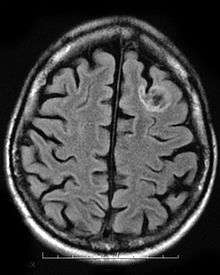

A dysembryoplastic neuroepithelial tumour is commonly diagnosed in patients who are experiencing seizures with magnetic resonance imaging (MRI), electroencephalogram (EEG).[4] A DNT is most commonly diagnosed in children who are experiencing seizures, and when given medication do not respond to them. When a MRI is taken there are lesions located in the temporal parietal region of the brain.[4]